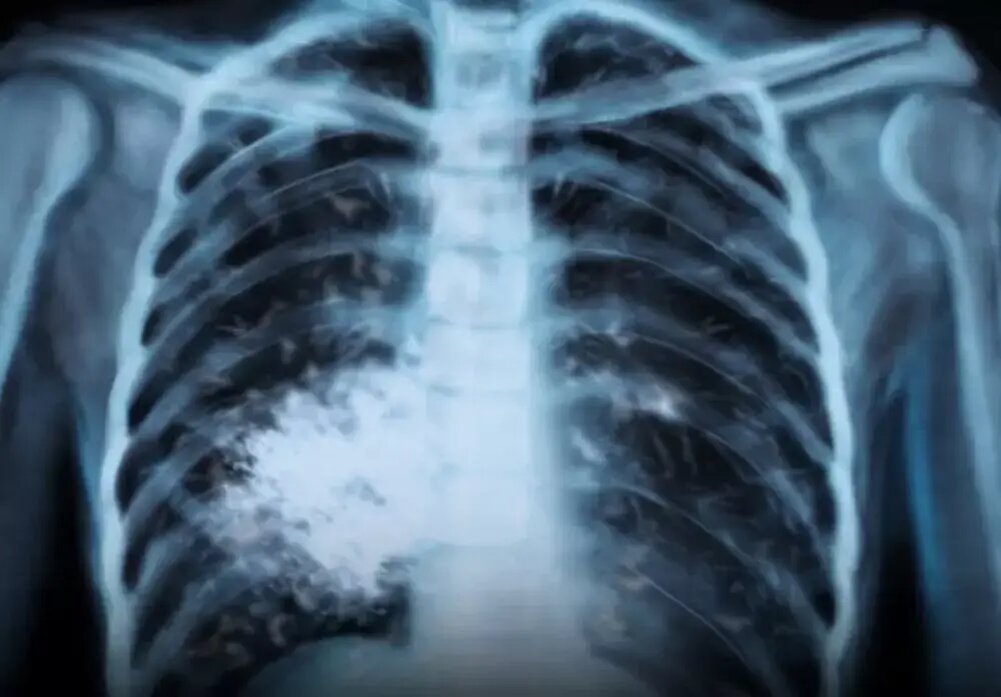

«Попкорновое лёгкое» у подростка: сладкий вейпинг обернулся необратимым повреждением дыхательных путей

Попкорновое легкое. Фото: СоцСети.

Речь идёт не о временном воспалении. Это хроническое и необратимое повреждение самых мелких дыхательных путей. Ткань бронхиол буквально рубцуется. Просвет сужается. Воздух проходит хуже - отсюда постоянный кашель, свист при дыхании, одышка даже в покое. И это уже на всю жизнь.